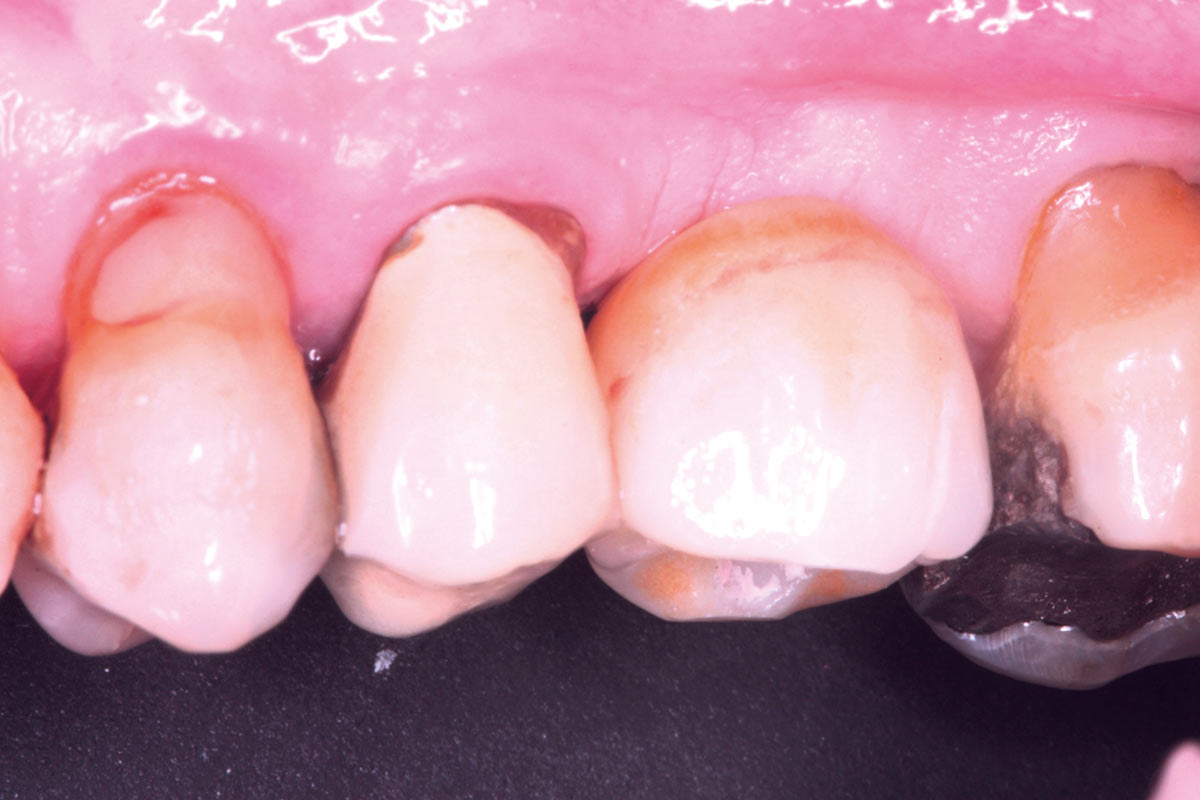

Initial view of the case. Discoloration of 1.1 and mild class I gingival recession